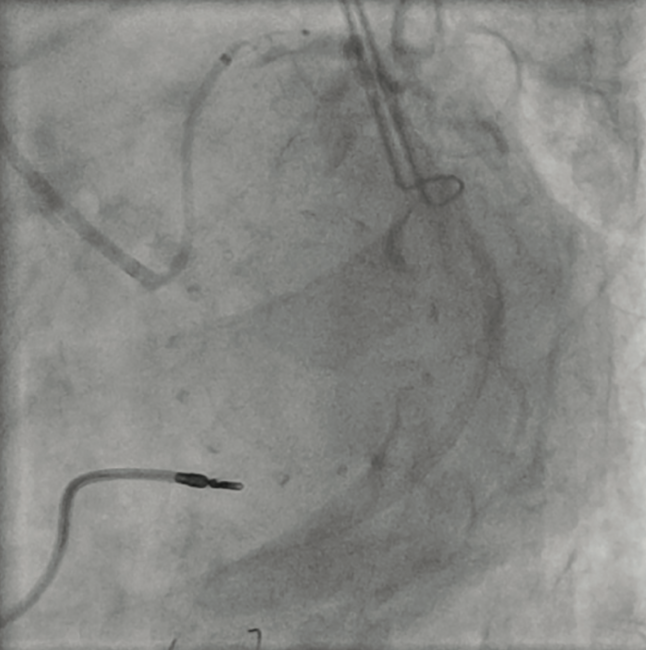

After gaining wire access to the LCx, support was increased by advancing a 5 Fr GuideLiner V3 guide extension (Teleflex) to the distal LM coronary artery. Unfortunately, even the combined support provided by the coronary guidewire and GuideLiner was not enough to allow engagement of the LM ostium with the guide. At this point, a NC Trek 2 mm x 12 mm balloon (Abbott Vascular) was advanced into the distal LM/proximal LCx and inflated to 5 atmospheres (atm) (Figure 2). With the help of this balloon anchoring, the guide catheter was gently lifted, then advanced into the ostial LM coronary artery (Figures 3-5). During this maneuver, gentle counter traction was placed on the shaft of our balloon catheter. After successful guide delivery to the LM coronary artery, the rest of the procedure was uneventful, with placement of a drug-eluting stent into the distal LM and proximal LCx with optimal angiographic result.